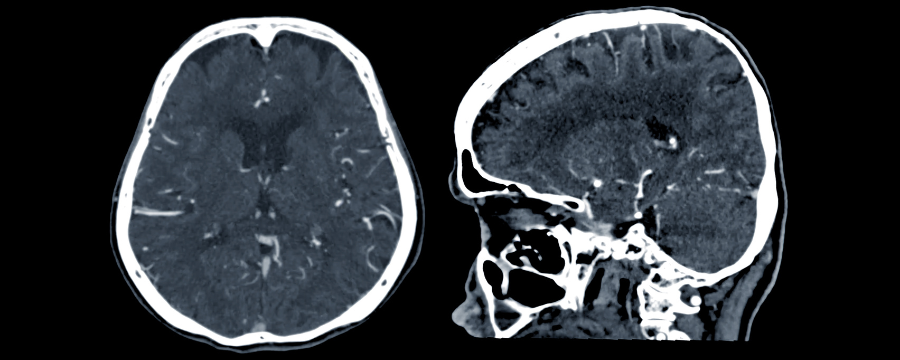

La Tomografía Axial Computarizada Cerebral es lo que conocemos como TAC cerebral. Una prueba en la que se utilizan rayos X para poder observar con detalle el cerebro. De esta manera, se pueden detectar tanto fracturas en el cráneo después de un accidente, hemorragias, localización de tumores o edemas.

Hay situaciones en las que puede que se necesite realizar un TAC con contraste para observar mejor los tejidos y estructuras que se van a observar. Sin embargo, hay que aclarar que esto no siempre es necesario, por lo que dependerá de las sospechas que se tengan, así como de la precisión que se requiera en las imágenes que se obtengan.

La Tomografía Axial Computarizada Cerebral es una prueba no invasiva y que, además, permite obtener imágenes rápidas y con gran detalle. Por lo tanto, es un instrumento muy utilizado en el ámbito médico para detectar lesiones, investigar síntomas neurológicos, etc.